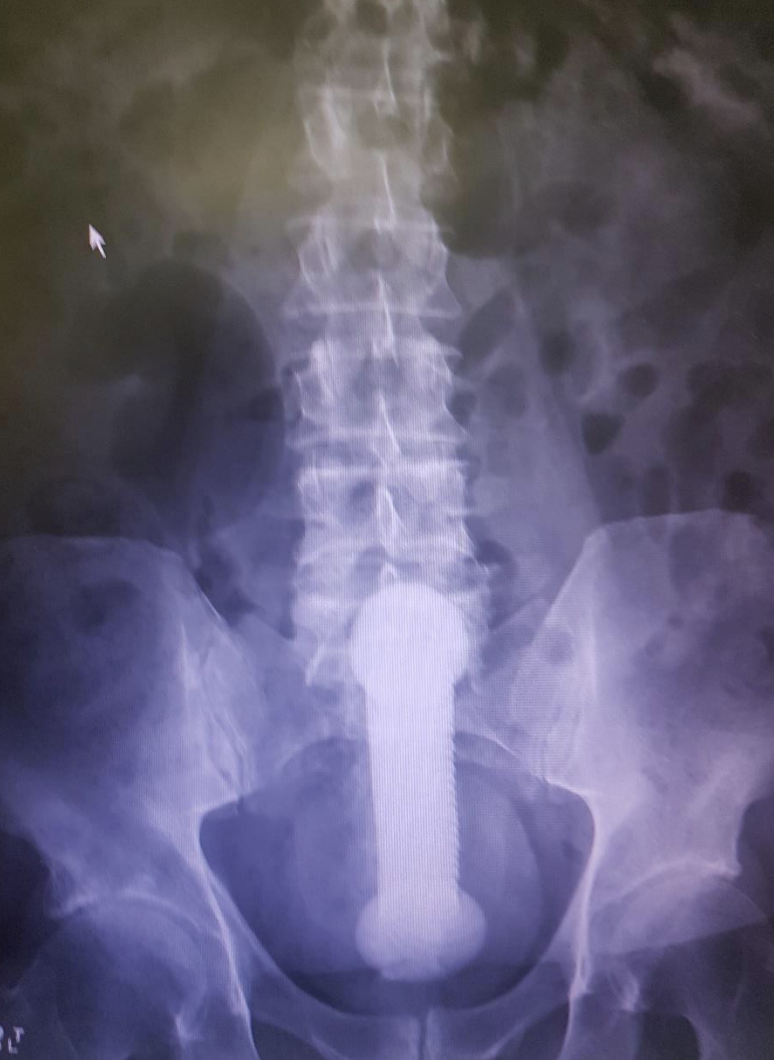

what are the anaesthesia options for removal in ED?

Non anaesthesia

A

Anaesthesia:

* regional anaesthesia - perianal block

* procedural sedation eg fent/prop

* valsalva with lubricant

* gentle traction with lubricant

* foley catheter wth 50ml balloon and lubricant